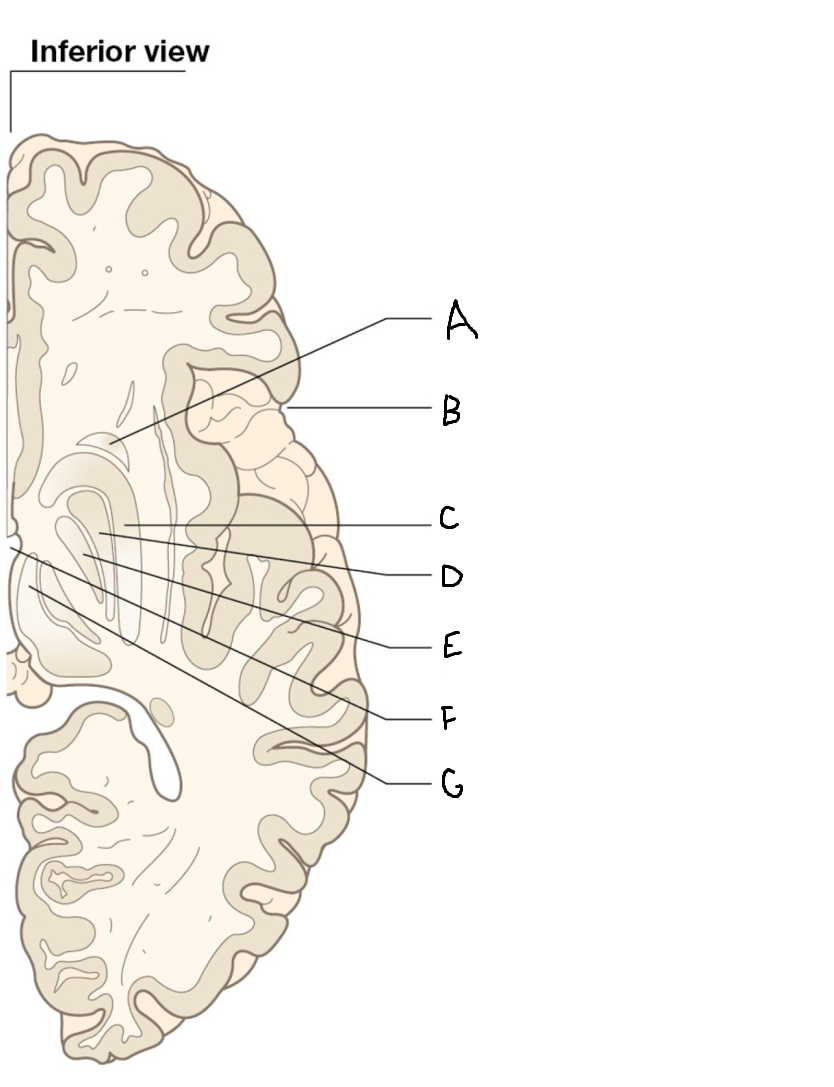

A

corpus callosum

B

lateral ventricle

C

internal capsule

D

third ventricle

E

tail of caudate nucleus

F

lateral ventricle

G

hippocampus

H

mammillary body

I

fornix

J

globus pallidus

K

putamen

L

caudate

M

thalamus

N